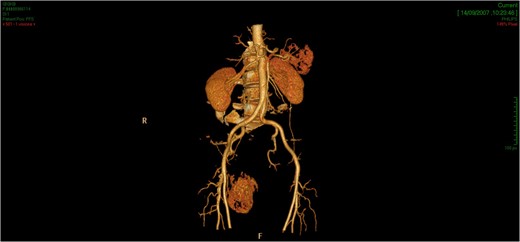

The tridimensional reconstruction shows the rich vascularization of the neoplasm.

Surgical treatment was carried out with a posterior approach (Fig. 5). The lesion was in close proximity of elevator ani muscle and lateral rectal wall, that were not macroscopically infiltrated. The lesion area was marked with surgical clips because of the close proximity with rectal wall, for eventual post-operative chemotherapy or radiotherapy and for follow-up. Surgical specimen was an oval, soft tissue mass of 11 × 7.5 × 5.5 cm in size, capsulated, hyper-vascularized, with a inhomogeneous aspect, multi-lobed (Fig. 6). Microscopically, the tumour was composed by a proliferation of spindle cells crossed by stromal collagen and giant plurinucleate cells. Neoplastic cells immunophenotype showed expression for CD34 and bcl-2 (Figs 7–9).